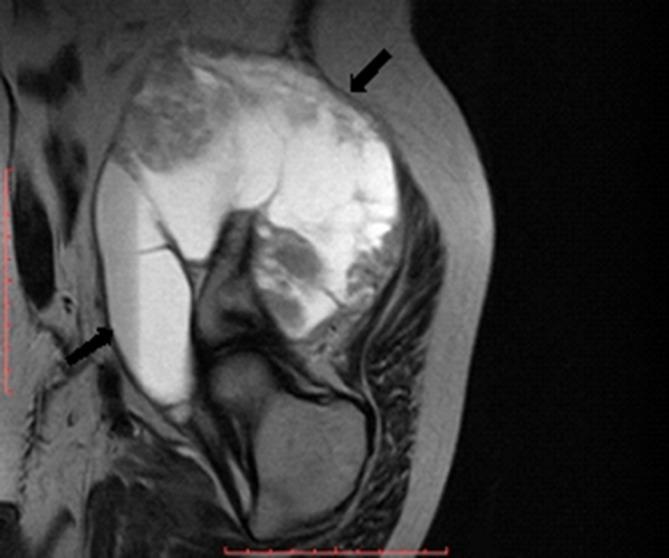

This report describes a huge chondromyxoid fibroma (CMF) that developed in the right iliac crest and wing. The tumour is rare, perhaps the rarest of all bone tumours, and its occurrence in the iliac crest and wing of a 63-year-old male is extraordinarily uncommon. The patient complained of gradual onset of right groin pain over a period of more than 2 years and low back pain and tender swelling of the right gluteal region over a period of another 1 year. Conventional radiography of the lumbar spine and pelvis revealed a large osteolytic lesion of the right iliac crest and wing associated with mild levoscoliosis. MRI of the pelvis revealed a huge well-defined lesion arising from the right iliac crest and wing and extending to the right paraspinal region, false pelvis and right gluteal region and displacing rather than invading the surrounding structures. The patient underwent surgery, and the mass was totally removed. The clinical manifestations, imaging findings and surgical treatment of the lesion are discussed.

本报告描述了一例发生于右髂嵴和髂骨翼的巨大软骨黏液样纤维瘤(CMF)。该肿瘤较为罕见,可能是所有骨肿瘤中最罕见的,其发生在一名63岁男性的髂嵴和髂骨翼极为少见。患者诉说在超过2年的时间里右腹股沟疼痛逐渐出现,在另外1年的时间里出现下背部疼痛以及右臀区域压痛性肿胀。腰椎和骨盆的传统X线摄影显示右髂嵴和髂骨翼有一个大的溶骨性病变,伴有轻度左旋脊柱侧弯。骨盆MRI显示一个巨大的边界清晰的病变,起源于右髂嵴和髂骨翼,延伸至右椎旁区域、假骨盆和右臀区域,推移而非侵犯周围结构。患者接受了手术,肿物被完全切除。本文讨论了该病变的临床表现、影像学表现及手术治疗。